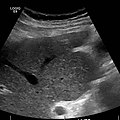

Doppler ultrasonography of the portal vein over 5 seconds, showing peaks of maximal velocity, as well as points of minimal velocity.

Ultrasound is routinely used in the evaluation of cirrhosis. It may show a small and nodular liver in advanced cirrhosis along with increased echogenicity with irregular appearing areas. Other liver findings suggestive of cirrhosis in imaging are an enlarged caudate lobe, widening of the fissures and enlargement of the spleen. An enlarged spleen (splenomegaly), which normally measures less than 11–12 cm in adults, can be seen and may suggest underlying portal hypertension. Ultrasound may also screen for hepatocellular carcinoma, portal hypertension, and Budd-Chiari syndrome (by assessing flow in the hepatic vein). An increased portal vein pulsatility is an indicator of cirrhosis, but may also be caused by an increased right atrial pressure.[33] Portal vein pulsatility can be quantified by pulsatility indices (PI), where an index above a certain cutoff indicates pathology: